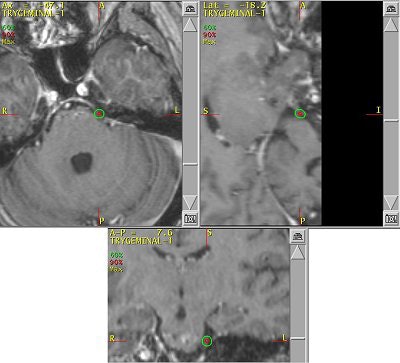

![]() |

| An example of a treatment plan for TN using a single isocenter to deliver a single fraction of 80 Gy to the TN nerve root. A single 5-mm collimator and a multiarc technique would be used to minimize dose to the brain stem. Image courtesy of Varian Medical Systems, Palo Alto, CA. |

These days, planning is done often with CT or MRI, with the latter used for planning and the former for treatment simulation. On the most basic level, all radiosurgery systems deliver high doses of ionizing radiation (65-90 Gy) to small intracranial targets via imaging guidance.